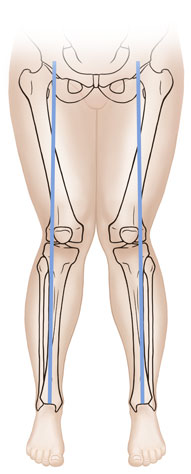

If your child’s legs curve outward, they have bowlegs. If your child’s knees come together and the lower legs point outward, they have knock knees. Often, a child will start out with bowlegs, the legs may straighten, then the child may become knock-kneed. Your healthcare provider will examine your child’s legs and may X-ray them to make sure there isn’t a structural problem.

| Knock knees. |